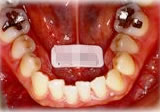

初診時年齢31歳7ヶ月。下顎側方偏位による咬合不全を主訴に来院。

顎変形と診断し、外科的処置を併用して治療。

上顎 上顎 上顎